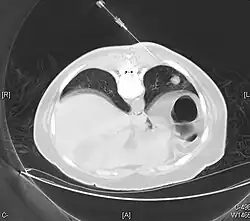

.jpg)

The definitive diagnosis is rendered by a microscopic examination, after excision. Typical carcinoids have cells with stippled chromatin and a moderate quantity of cytoplasm. They typically have few mitoses and lack necrosis. By definition, they are greater than 4 mm in largest dimension; smaller lesions are referred to as pulmonary carcinoid tumourlets.